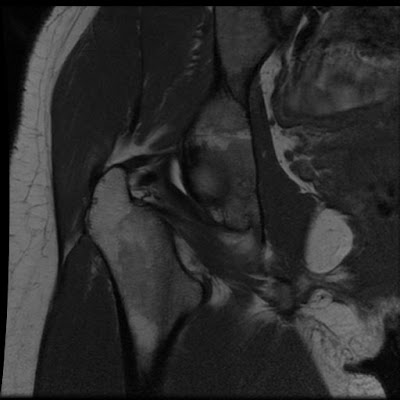

Postero-Superior Labral tear